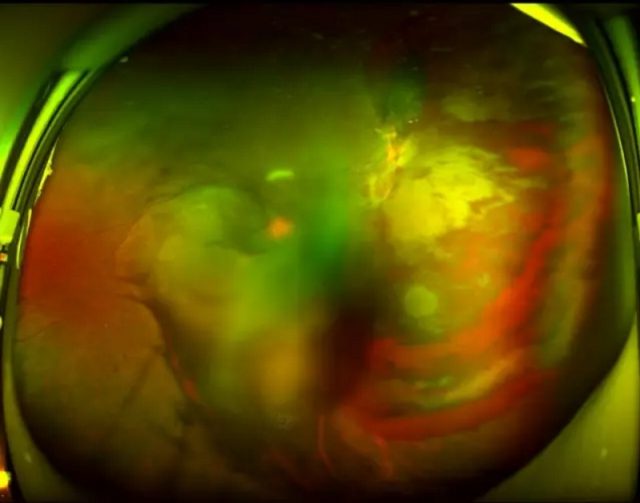

「釉 里 红」包头朝聚眼科医院昆区门诊部